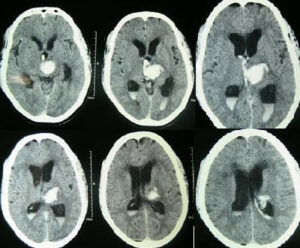

CT-scan of a frontal intracerebral hemorrhage on the right (left image side) as a contre coup. There is dens suture material visible left occipital in the skin.

Brain trauma CT. - Primary brain injuries, Secondary brain injuries

Post-Traumatic Secondary Injury Cascades. - Brain Hematomas (Epidural hematoma, Subdural hematoma, Intracerebral hematoma)

Cranial Hemorrhages.

Acute Epidural Hematoma.

CT brainAVM non-contrast hematoma.

Hematoma Comparison.

Ct-scan of the brain with an subdural hematoma.

Chronic subdural bleed with old burr holes.